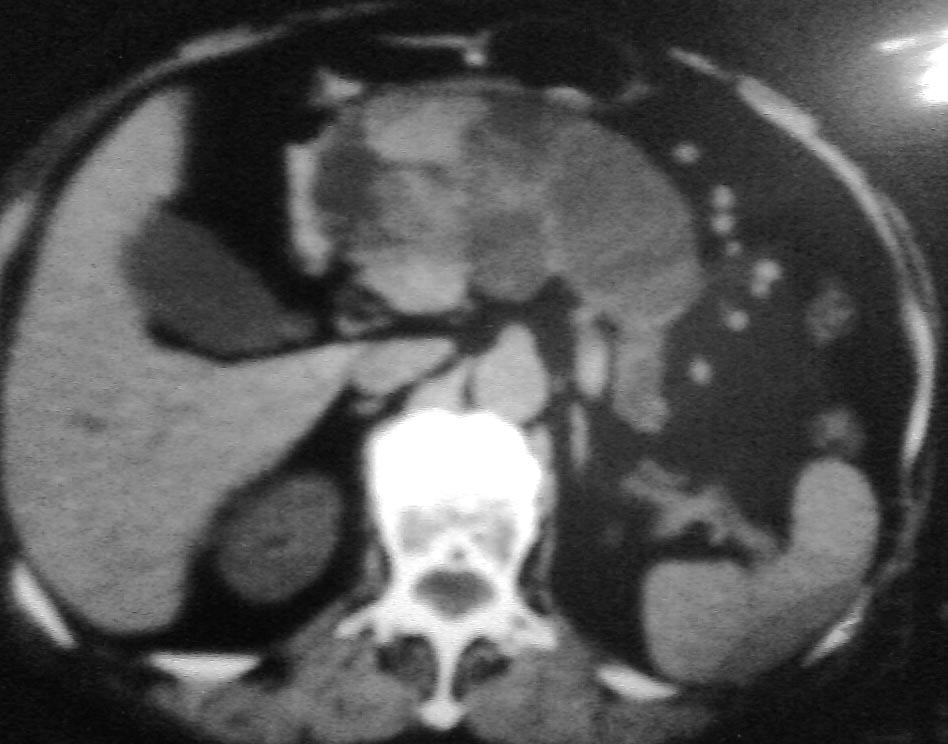

上腹部不适半年左右,体检此区压痛,精神状态很好,谢各位给个意见!

与中国医学影像网中“今日病例”(12-2)类似——胰管乳头状粘液瘤。

考虑胰腺黏液腺癌.低度恶性.

考虑胰管乳头状粘液瘤

胰腺占位病灶

1与中国医学影像网中“今日病例”(12-2)类似——胰管乳头状粘液瘤

2考虑胰腺黏液腺癌.低度恶性.